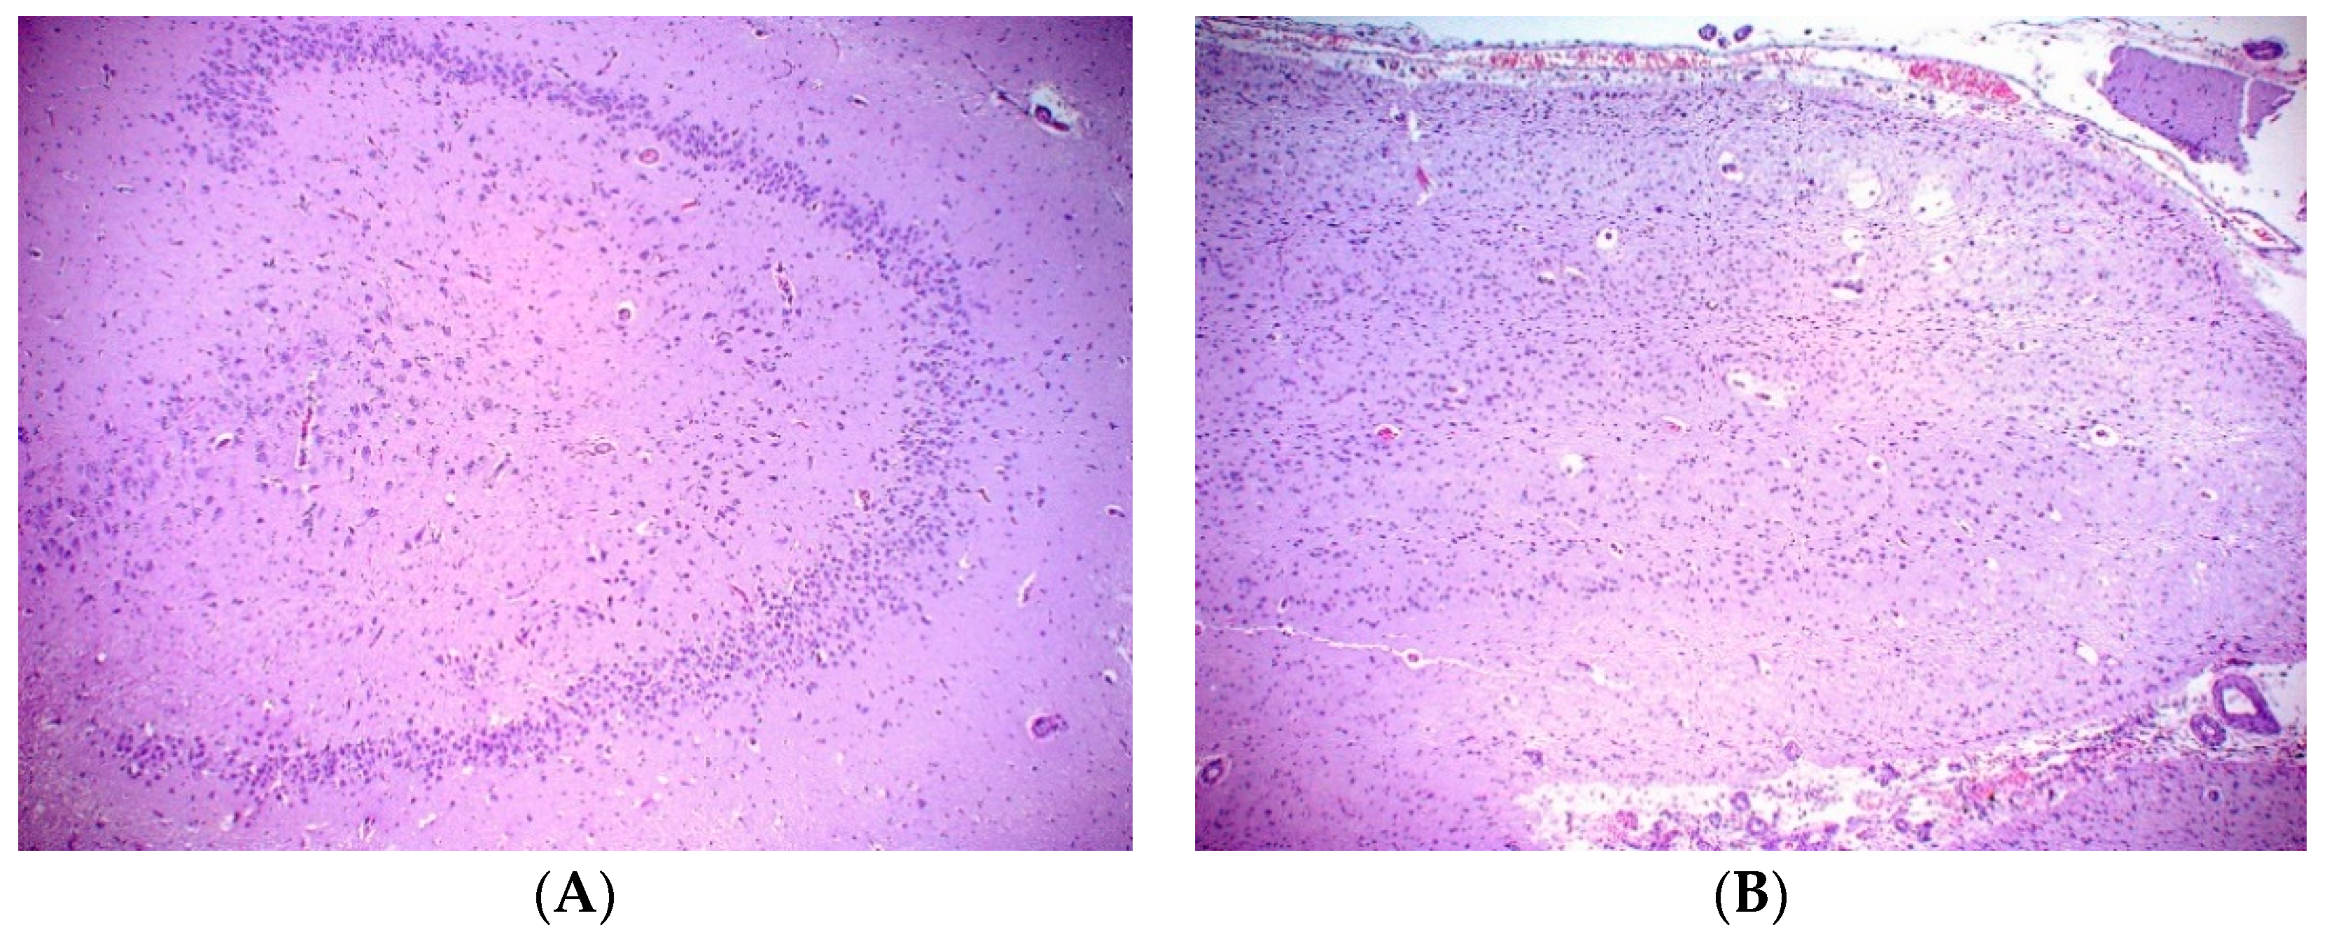

A necropsy examination was conducted within hours after humane euthanasia and found the animal to be in good nutritional condition weighing 148 kg. Gross findings included mild mottling of the lung parenchyma, mild liver lobe congestion on the recumbent side and mottled gastrointestinal serosa. The most significant histopathologic finding was chronic marked to severe atrophy of the right hippocampus and right temporal lobe. There was also chronic mild atrophy of the left hippocampus. The right dentate gyrus was not present, but instead consisted of reduced loose neuropil and large astrocytes with small numbers of poorly organized neurons compared to the left dentate gyrus (Figure 1). All findings are consistent sequelae from chronic domoic acid toxicity [21]. There was additionally focal chronic severe necrosis and atrophy of distal cerebellar folia, with acute hemorrhage with no cause identified. There was no microscopic evidence of any previous or ongoing infectious or inflammatory disease in the brain or other tissues. While domoic acid exposure has additional documented adverse effects to the myocardium that often progresses to degenerative cardiomyopathy, there was no microscopic evidence of persistent damage to the heart related to previous DA exposure and no microscopic evidence of cardiac insufficiency in this fur seal case [21,22].

Figure 1. (A) Left dentate gyrus with mildly reduced cellularity. HE, 10×. (B) Right dentate gyrus with chronic necrosis and atrophy present. HE, 10×.